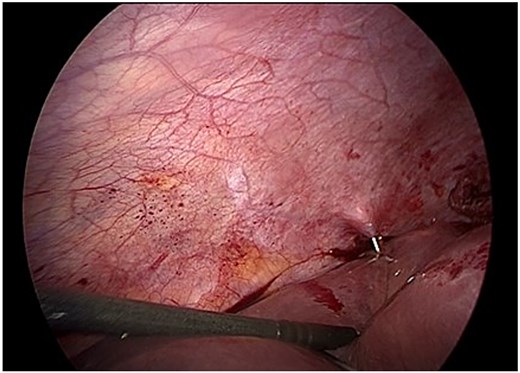

The laparoscopic procedure was performed using four trocars. The operative field was protected with gauze soaked in 17.7% hypertonic saline to reduce the risk of peritoneal dissemination. The cyst was punctured, and a scolicidal agent (17.7% hypertonic saline) was instilled into the cavity and retained in situ for 15 minutes before aspiration. A secondary suction device was used to minimize leakage (Fig. 2).

Intraoperative view of controlled puncture and aspiration of cyst contents. Gauze soaked in 17.7% hypertonic saline protects the operative field to prevent spillage.